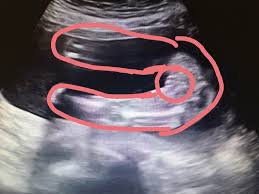

Nub Theorie Ssw 13 Forum Schwangerschaft Urbia De